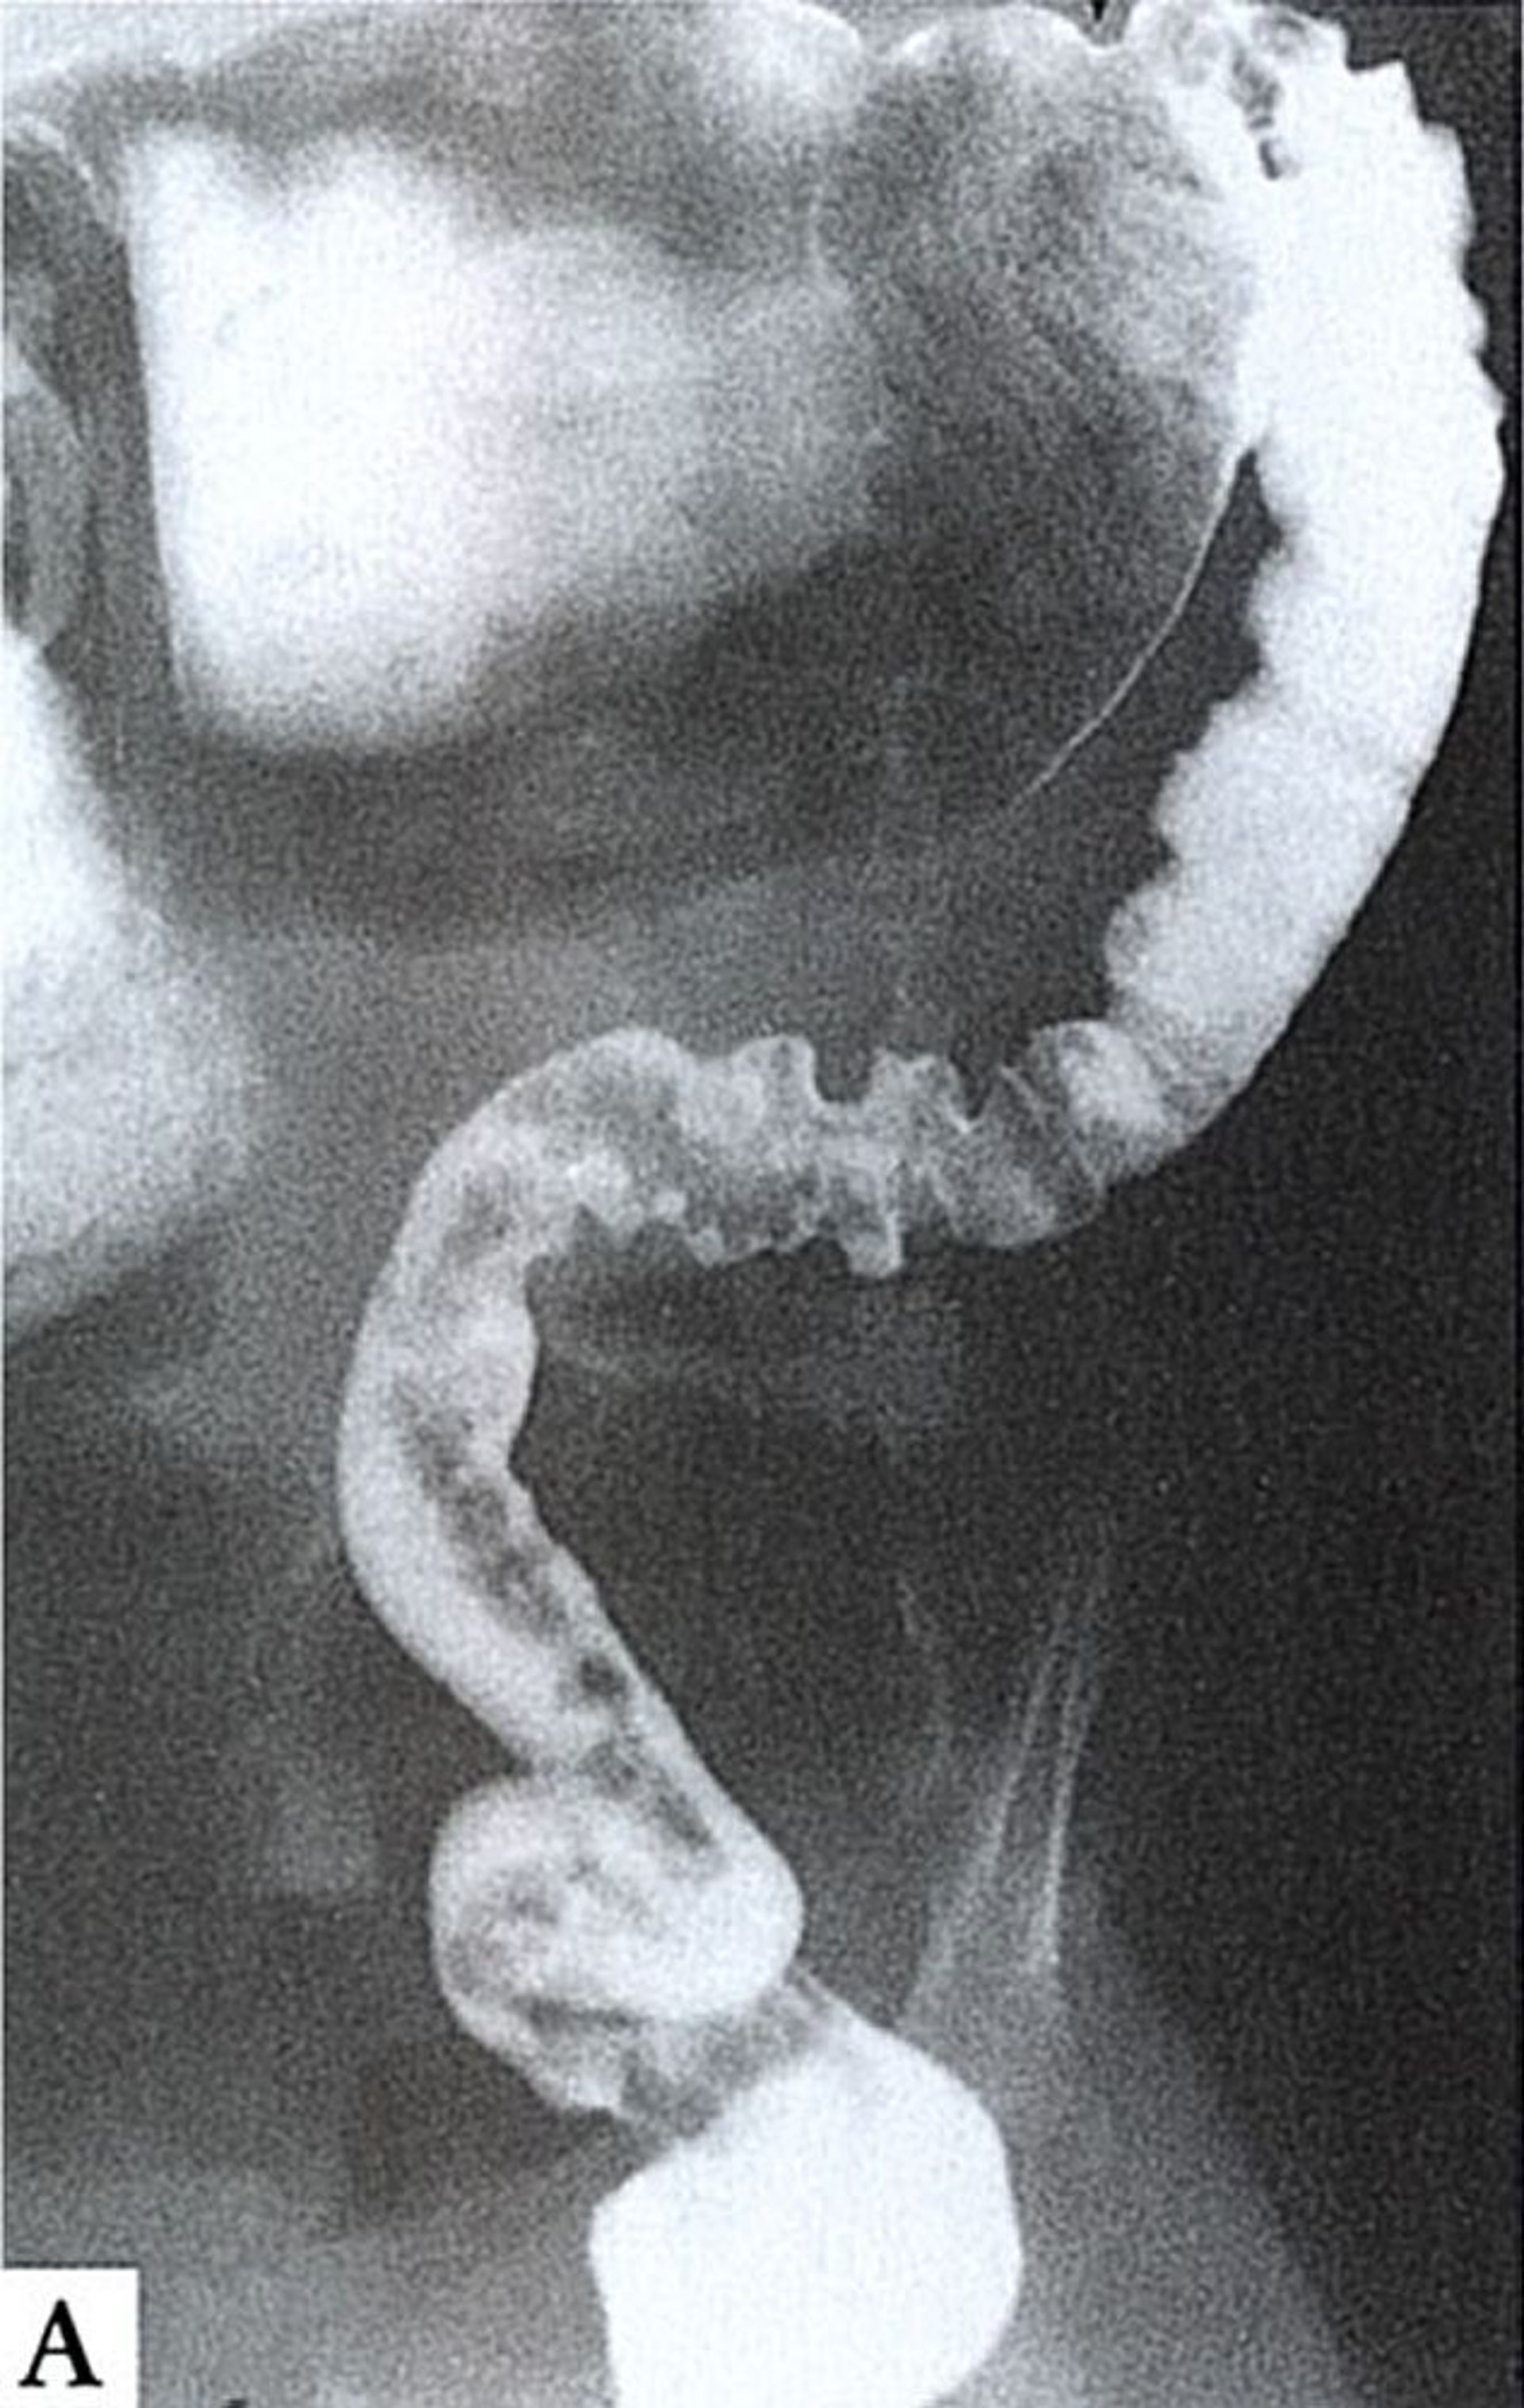

Ce lavement baryté montre une aganglionose qui va jusqu'à l'angle colique gauche. L'intestin aganglionnaire est rétréci et spastique (à droite), alors que l'intestin proximal normalement innervé (en haut) est dilaté et rempli de matières fécales.

By permission of the publisher. From Wald A: Gastroenterology and Hepatology: Colon, Rectum, and Anus. Edited by M Feldman (series editor) and CR Boland. Philadelphia, Current Medicine, 1996.